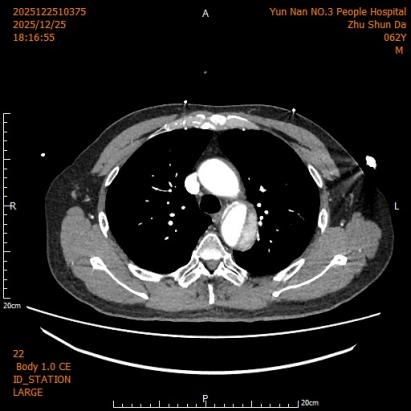

第二例患者诊断为胸腹主动脉夹层(Debakey Ⅲ型,逆向撕裂至主动脉弓部)。治疗团队先行采取非手术方案促进血肿吸收,再限期行腔内修复术。术中运用院内新技术“支架体外开窗”,成功保留了左侧锁骨下动脉血供;同时,腹主动脉覆膜支架采用术中自制微孔设计,在实现真腔扩大的同时,进一步减少了对脊髓血供的影响。

第二例患者术前CT